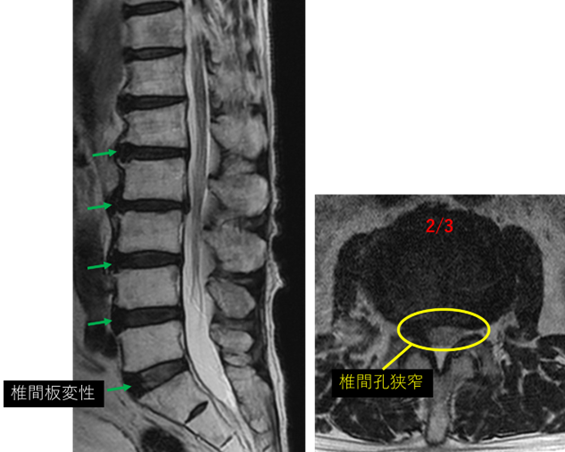

画像及び所見について

L1/2: 椎間板変性

L2/3: 椎間板変性、右ヘルニア、右椎間孔狭窄

L3/4: 椎間板変性

L4/5: 椎間板変性、膨隆

L5/S: 異常なし

以上の事が画像上認められます。

L1/2、2/3、3/4、4/5 に

椎間板変性、膨隆、右ヘルニア、右椎間孔狭窄 を認め、主症状の原因の可能性が高い。